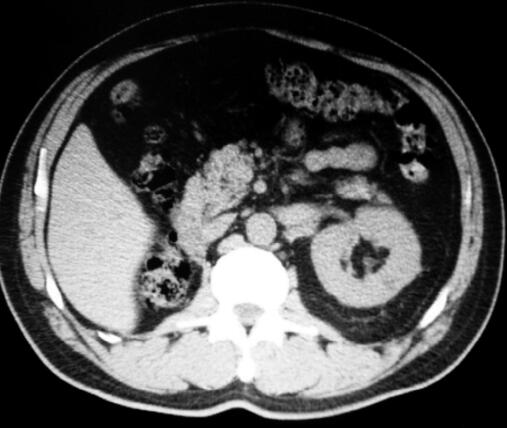

2.全腹CT(2011年12月28日):左肾可见一类圆形低密度影,直径约0.8cm,其内CT值为15HU,扫描范围内右肾未见显示,其他肝脏、脾脏、胆囊、胰腺、膀胱、前列腺均正常,腹膜后及盆腔未见增大淋巴结。诊断建议:左肾小囊肿,右肾缺如,术后改变(图2)。

图2